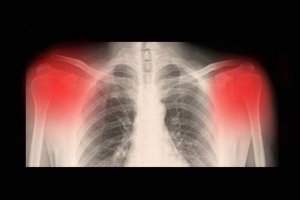

Tipik olarak, tanı klinik test yoluyla yapılabilir. Normalde, bu test, x-ışınları, BT ya da bir MR ile yapılmaktadır. Ayrıca, osteoartritinizin hangi seviyede olduğu da yüksek çözünürlüklü ultrason ile tespit edilebilir.